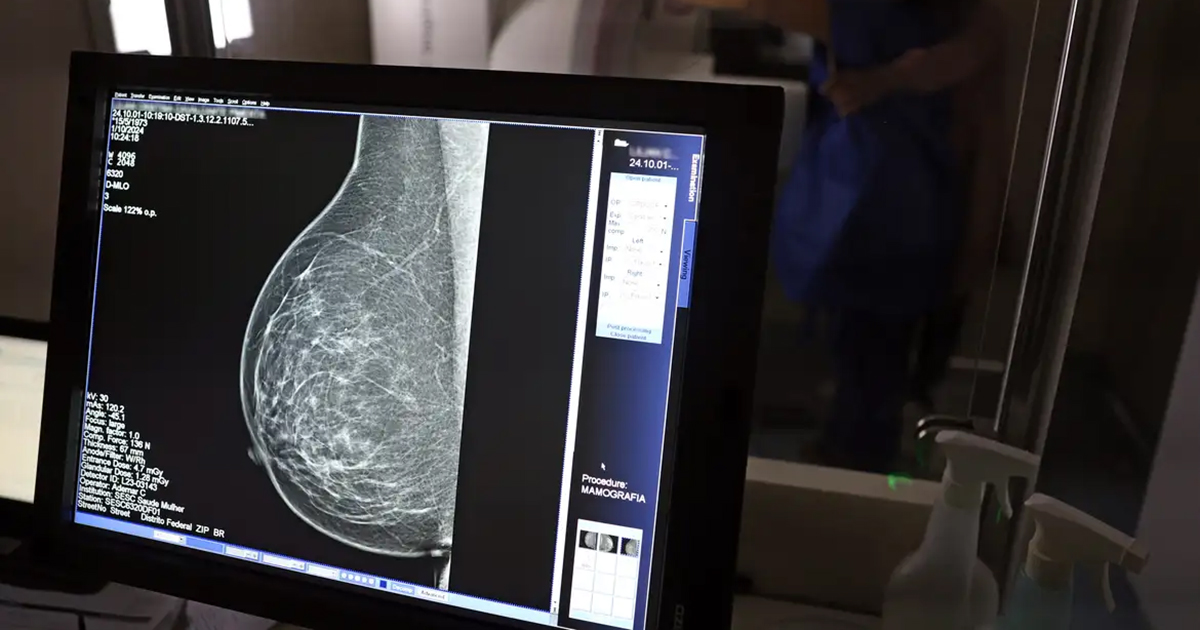

Tecnologia do micro-ondas é alternativa confortável à mamografia tradicional

Um novo dispositivo para exames das mamas, que utiliza micro-ondas em vez de radiação ionizante, está sendo desenvolvido por pesquisadores da Escola Politécnica (Poli) da Universidade de São Paulo (USP) e do Instituto Federal de São Paulo (IFSP). Ainda em fase de protótipo, a tecnologia promete ser uma alternativa menos dolorosa e mais acessível à mamografia tradicional.